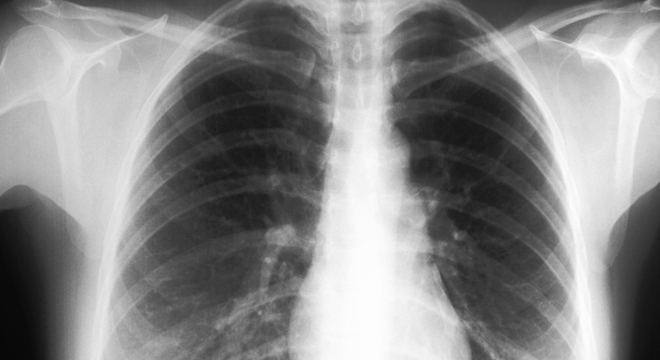

Brustfellentzündung: Röntgenbild der Lunge

Zur Diagnose einer Brustfellentzündung werden verschiedene Untersuchungen und Abklärungen durchgeführt. Dazu gehören unter anderem:

• Röntgenaufnahme des Brustkorbes (Thorax): Pleuraerguss wird sichtbar